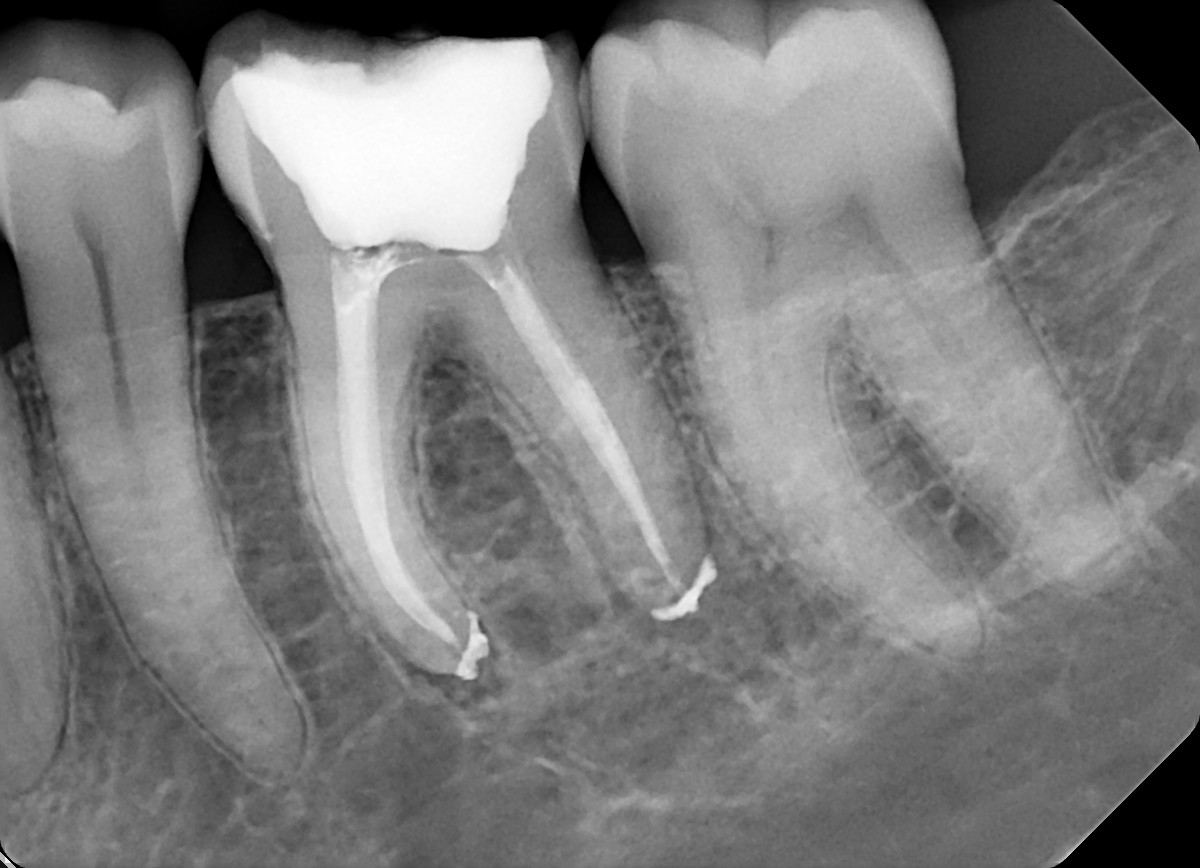

7. What condition can be selected or the root canal treatment of tooth # 4.6?

8. What condition can be selected or the root canal treatment of tooth # 3.6?